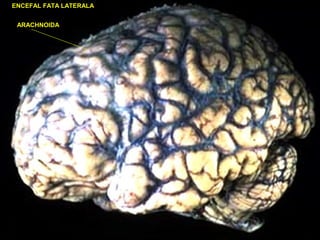

ENCEFAL FATA LATERALA

ARACHNOIDA